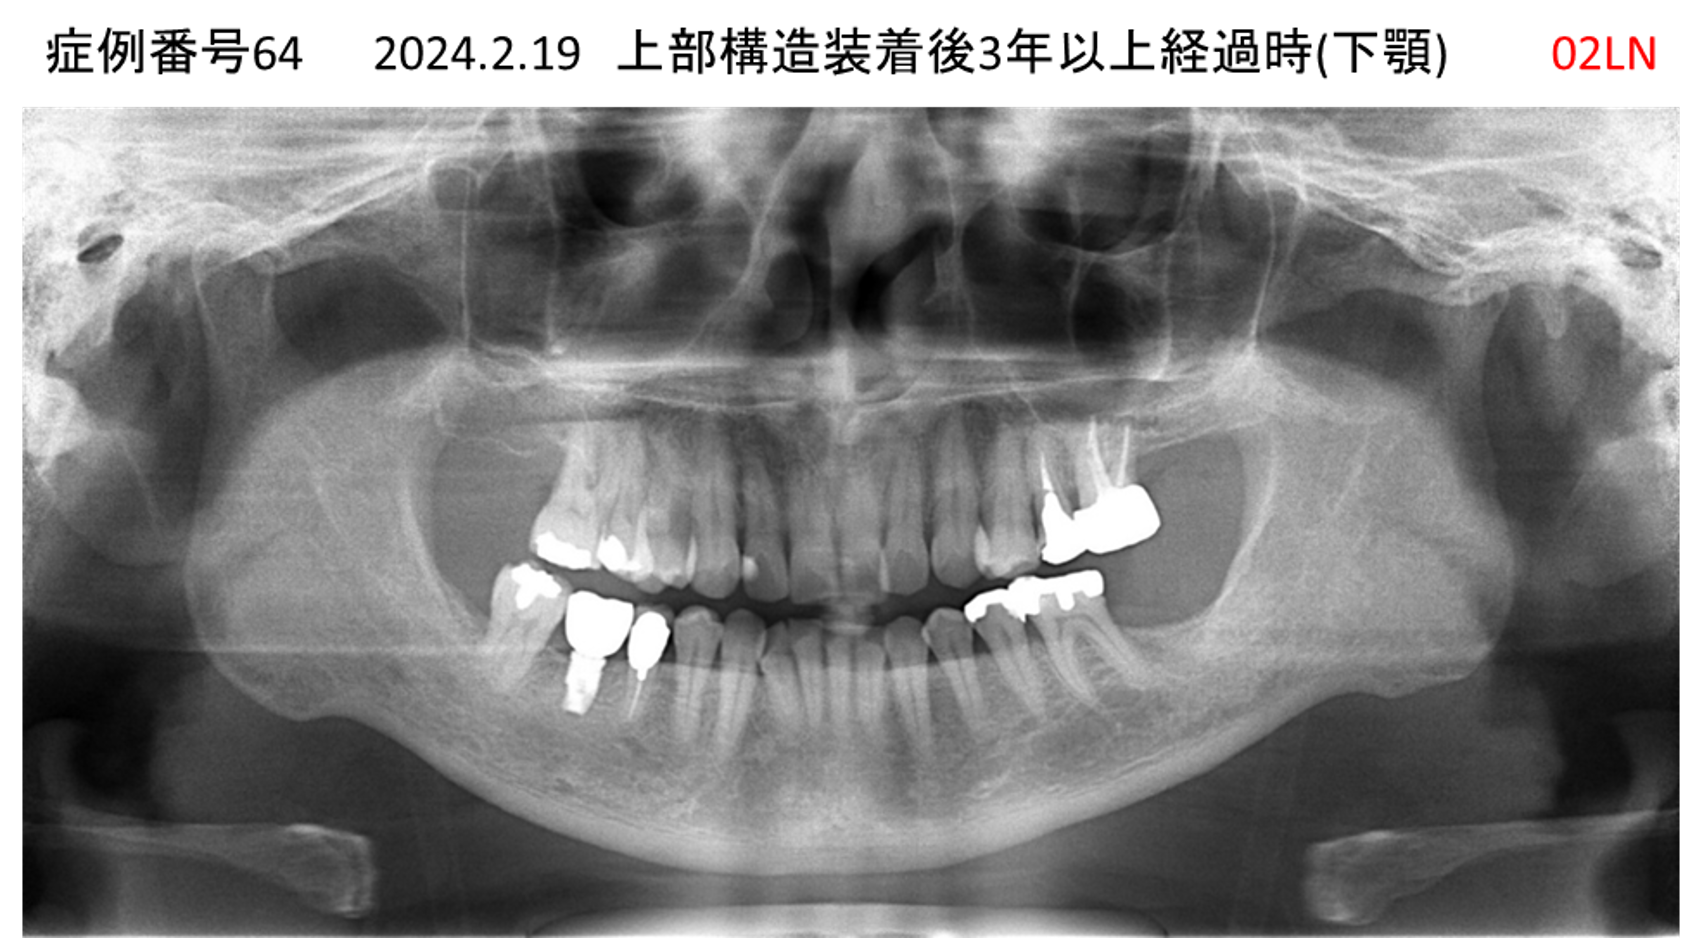

奥歯で噛めない患者様のインプラント症例

| 治療名称 |

インプラント |

| 治療費用 |

365万円+税 |

| 治療期間 |

5か月 |

| 患者さんの症状(主訴) |

奥歯で噛めない。上の前歯が揺れてきた。 |

| 治療内容 |

抜歯即時インプラント |

| 治療結果 |

食事に困らない。見た目がとても良くなった。 |

| 治療の注意点(リスク/副作用) |

インプラントが壊れたら再治療が必要 |